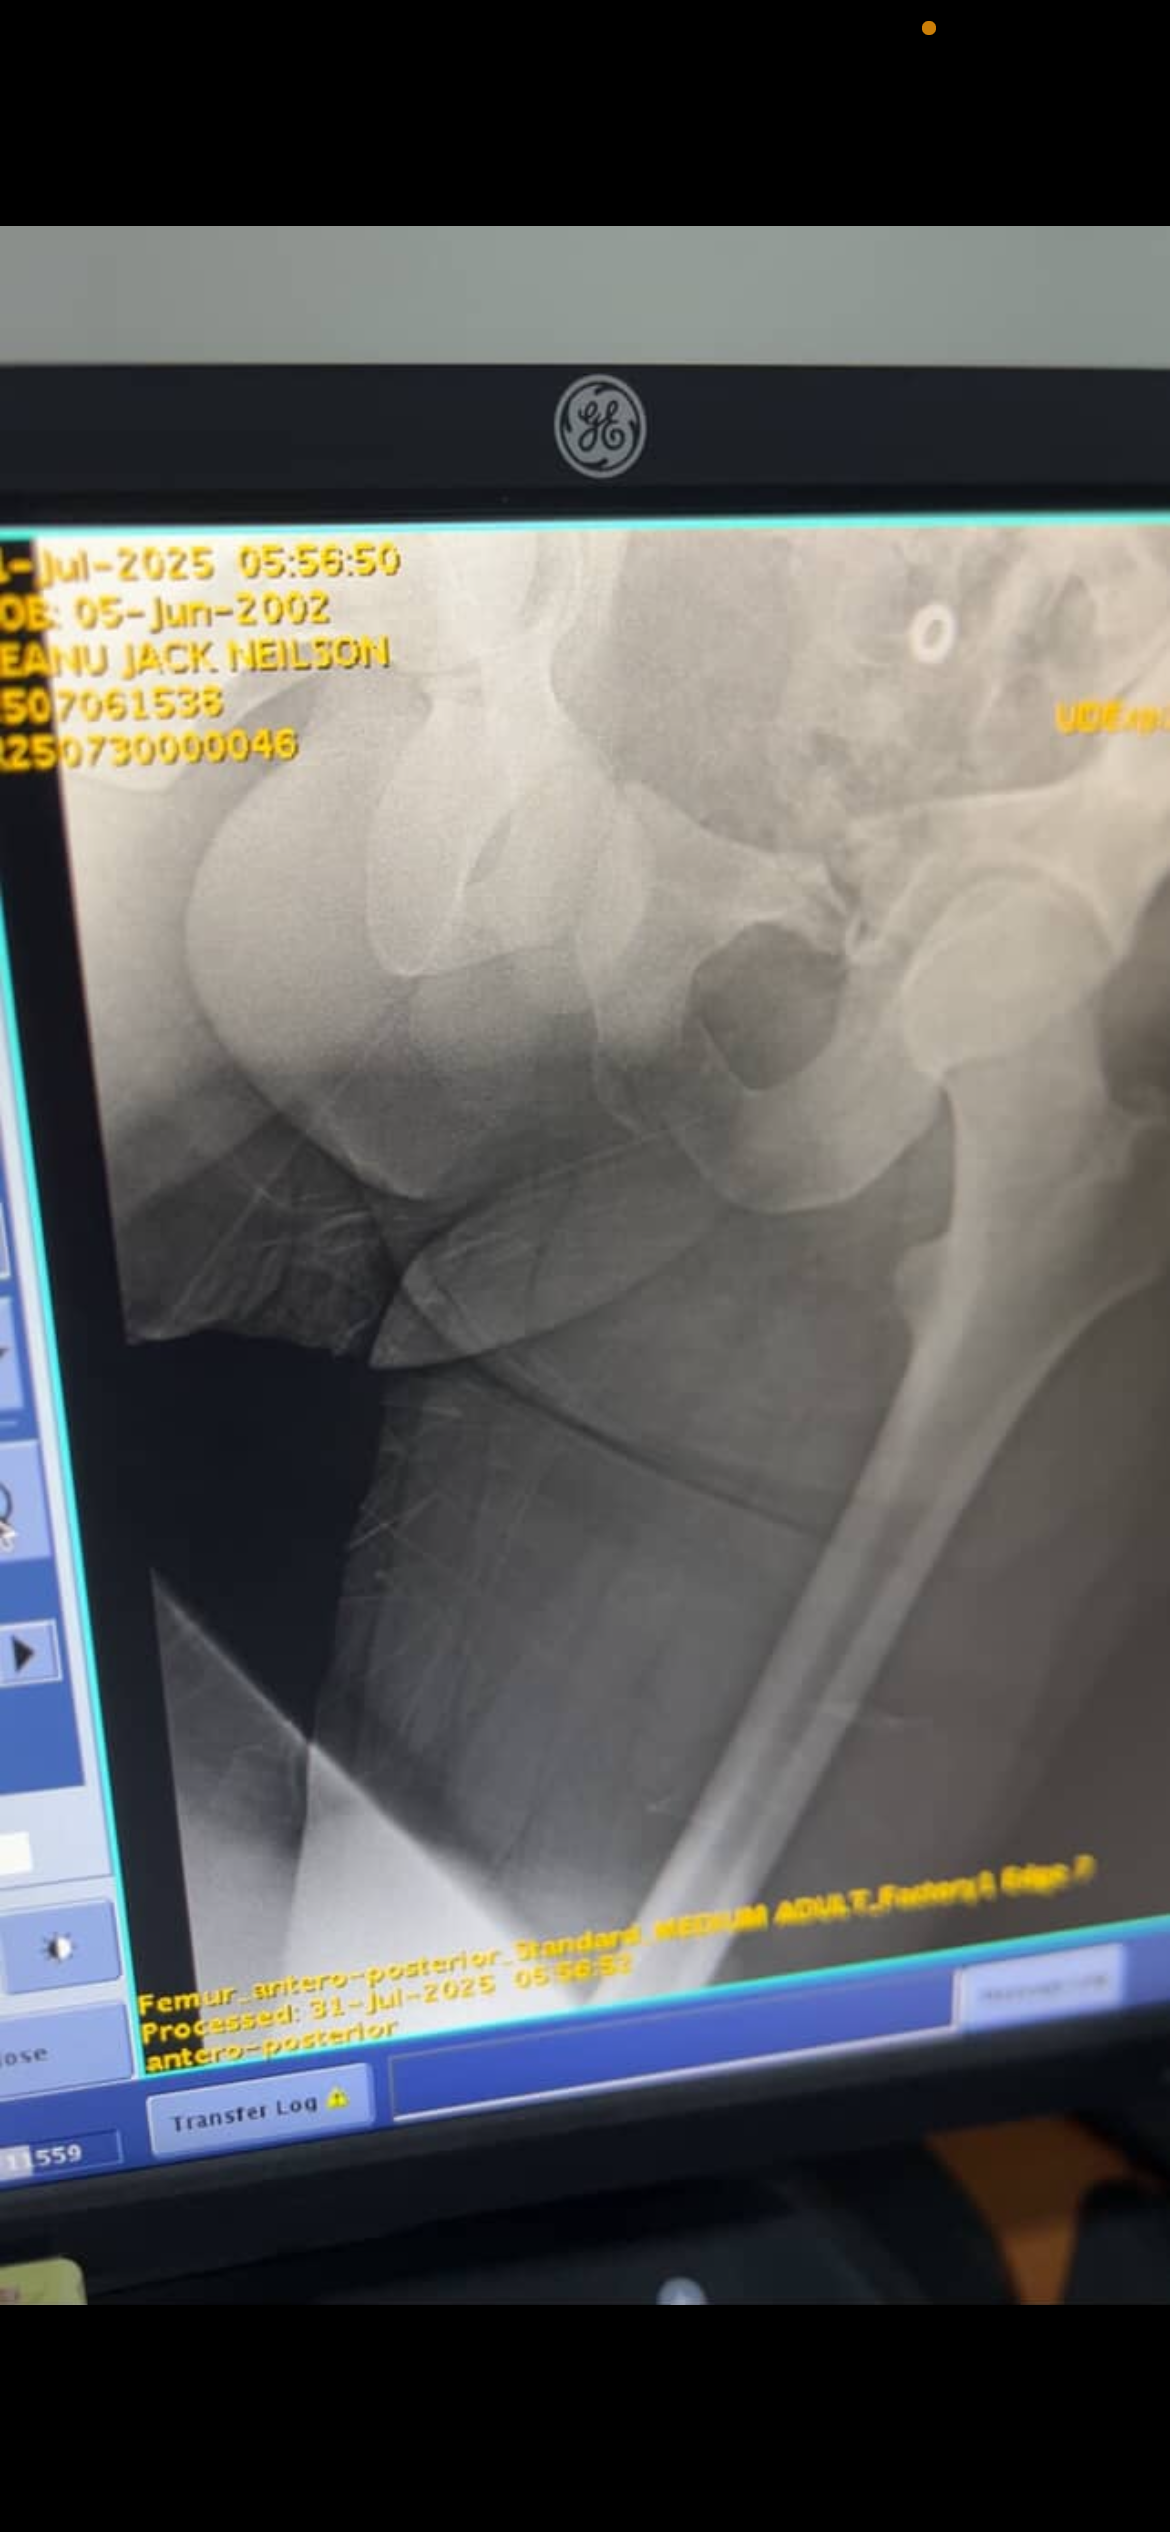

I’m reaching out with an urgent plea for help. My dear friend, Keanu Neilson was recently involved in a devastating scooter accident while in Bali — and is now fighting for his life.

He is currently heavily sedated, with multiple broken bones, including life-threatening internal injuries.